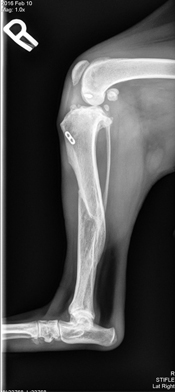

FasTak stabilization was performed on the right knee to stop cranial drawer. With this technique a strong line is secured between the femur and tibia using an absorbent screw. This technique works best in smaller breed dogs and when the tibial slope is relatively low. Scruffy went home the next day and his foster Mom worked hard to re-train his muscle and keep his exuberance controlled so that both of his knees could heal.